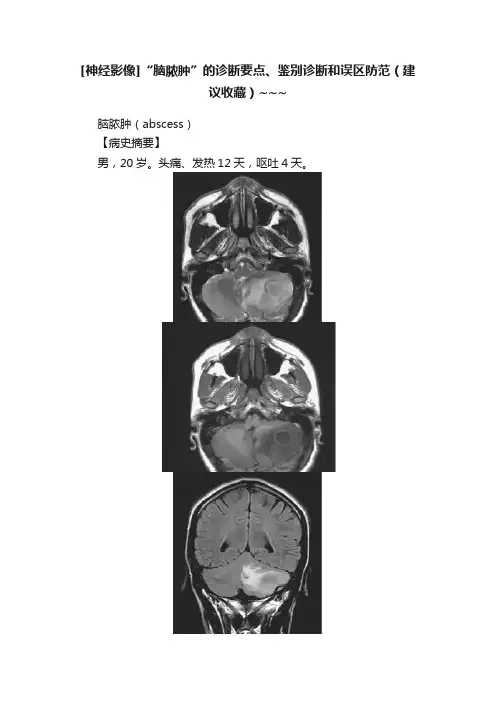

[神经影像]“脑脓肿”的诊断要点、鉴别诊断和误区防范(建议收藏)~~~脑脓肿(abscess)【病史摘要】男,20岁。

头痛、发热12天,呕吐4天。

图1脑脓肿MRI检查【影像所见】图1A、B,左侧小脑半球囊性占位病变,周围水肿明显,于T2WI 呈高信号、T1WI呈稍低信号,T2WI显示囊壁呈稍低信号。

图1C,冠状面T2 Flair显示灶周水肿明显。

图1D,矢状面T1WI显示病灶呈多环状。

图1E、F,增强扫描病变呈明显多个环状强化。

【诊断和分析】本病例诊断为脑脓肿。

影像学诊断要点:①脓肿壁形成,标志着脓肿的形成,脓肿壁在T1WI呈等或稍高信号,T2WI呈相对低信号,增强后脓肿壁强化,呈花环状改变,皮质侧较厚,脑室侧较薄,脓肿壁的T2WI低信号可能是巨噬细胞吞噬顺磁性自由基所致;②脓肿呈低信号,T2WI呈高信号,DWI上为高信号;③周围水肿带,T1WI呈低信号,T2WI呈高信号。